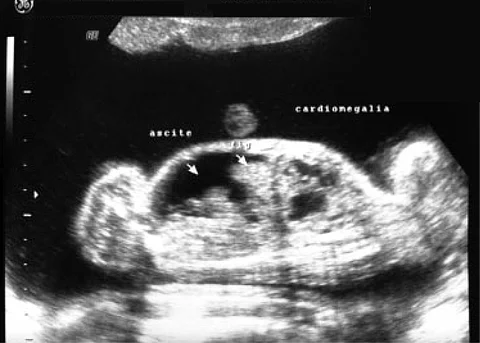

Eine 38-jährige Frau ist nach spontaner Empfängnis schwanger mit monochorioten, diamnioten Zwillingen. Ihre Krankengeschichte umfasst eine Wirbelsäulenentzündung und Tagesschläfrigkeit.